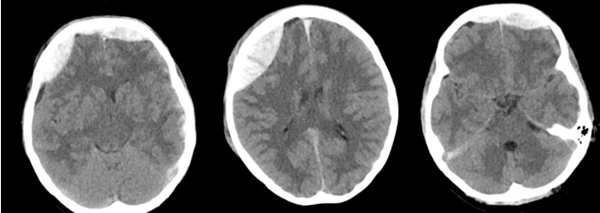

2025/09近日,中山大学附属第一医院(简称中山一院)广西医院神经外科团队成功救治一名因外伤导致迟发性硬膜外血肿的患者,经开颅硬膜外血肿清除术后,患者最终康复出院,并为科室送来一面写有“医术精湛挽危厄,仁心厚德臻至善”字样的锦旗,表达对科室全体医护人员感谢。患者黄女士(化名)是一名警员。因意外受伤被送到我院急诊科救治。我院立即启动绿色通道,为患者进行全面检查,头颅CT提示,额骨、右顶骨有20...